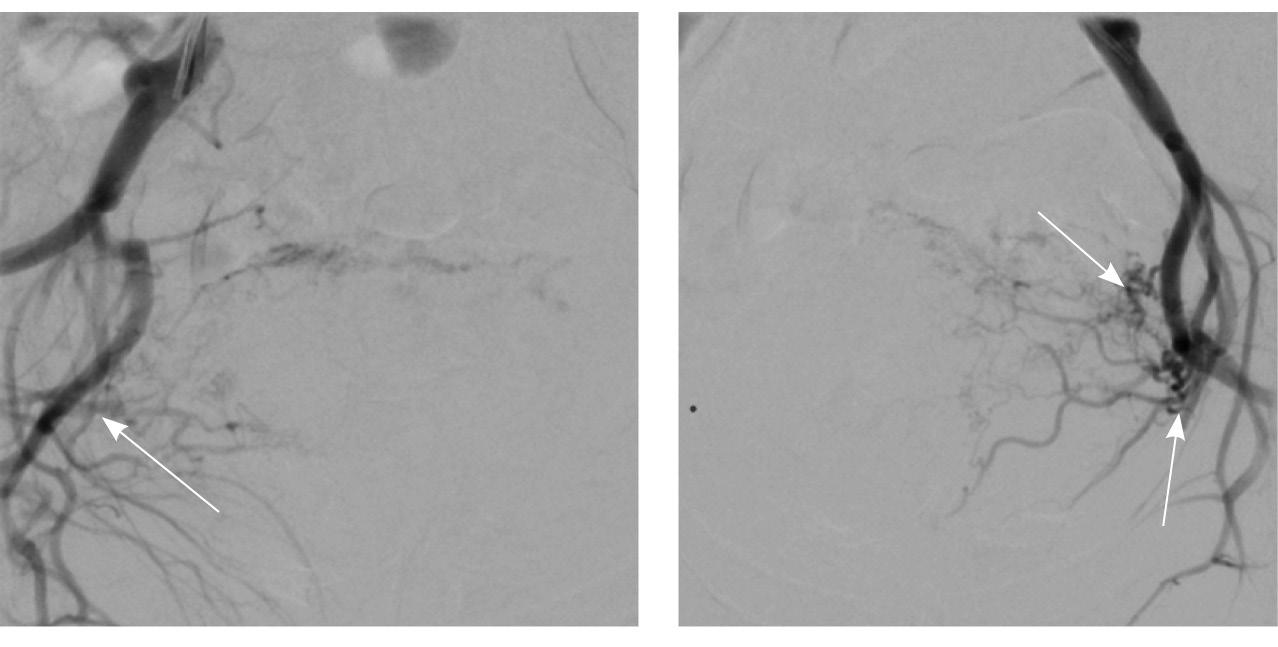

Исходя из клинической и визуальной картины, пациентке выполнено оперативное лечение. Первым этапом проведена эмболизация маточных артерий. Под местной анестезией раствором ропивакаина пунктирована правая лучевая артерия. Установлен интродьюсер 5F. Катетером НН последовательно катетеризированы левая и правая внутренние подвздошные артерии, выполнена ангиография. На ангиограммах: артериовенозная мальформация в проекции матки; афферентные артерии – маточные и цервиковагинальные – с обеих сторон, две ветви 1 мм в диаметре от левой внутренней подвздошной артерии; эфферентные сосуды – вены параметрия, внутренние подвздошные вены и яичниковые вены с обеих сторон (рис. 4).

Рис. 4. Данные рентгеноконтрастной ангиографии. А, Б – ангиограммы бассейнов правой и левой маточных артерий. Зоны патологической васкуляризации в проекции тела матки: массивная сеть измененных артерий и вен, ранний артериовенозный сброс в вены параметрия, внутренние подвздошные вены и яичниковые вены с обеих сторон. В, Г – ангиограммы бассейнов правой и левой цервиковагинальных артерий. Контрастирование зоны патологической васкуляризации в проекции шейки и нижнего отдела тела матки, ранний артериовенозный сброс в вены параметрия преимущественно слева и в левую внутреннюю подвздошную вену (стрелки)